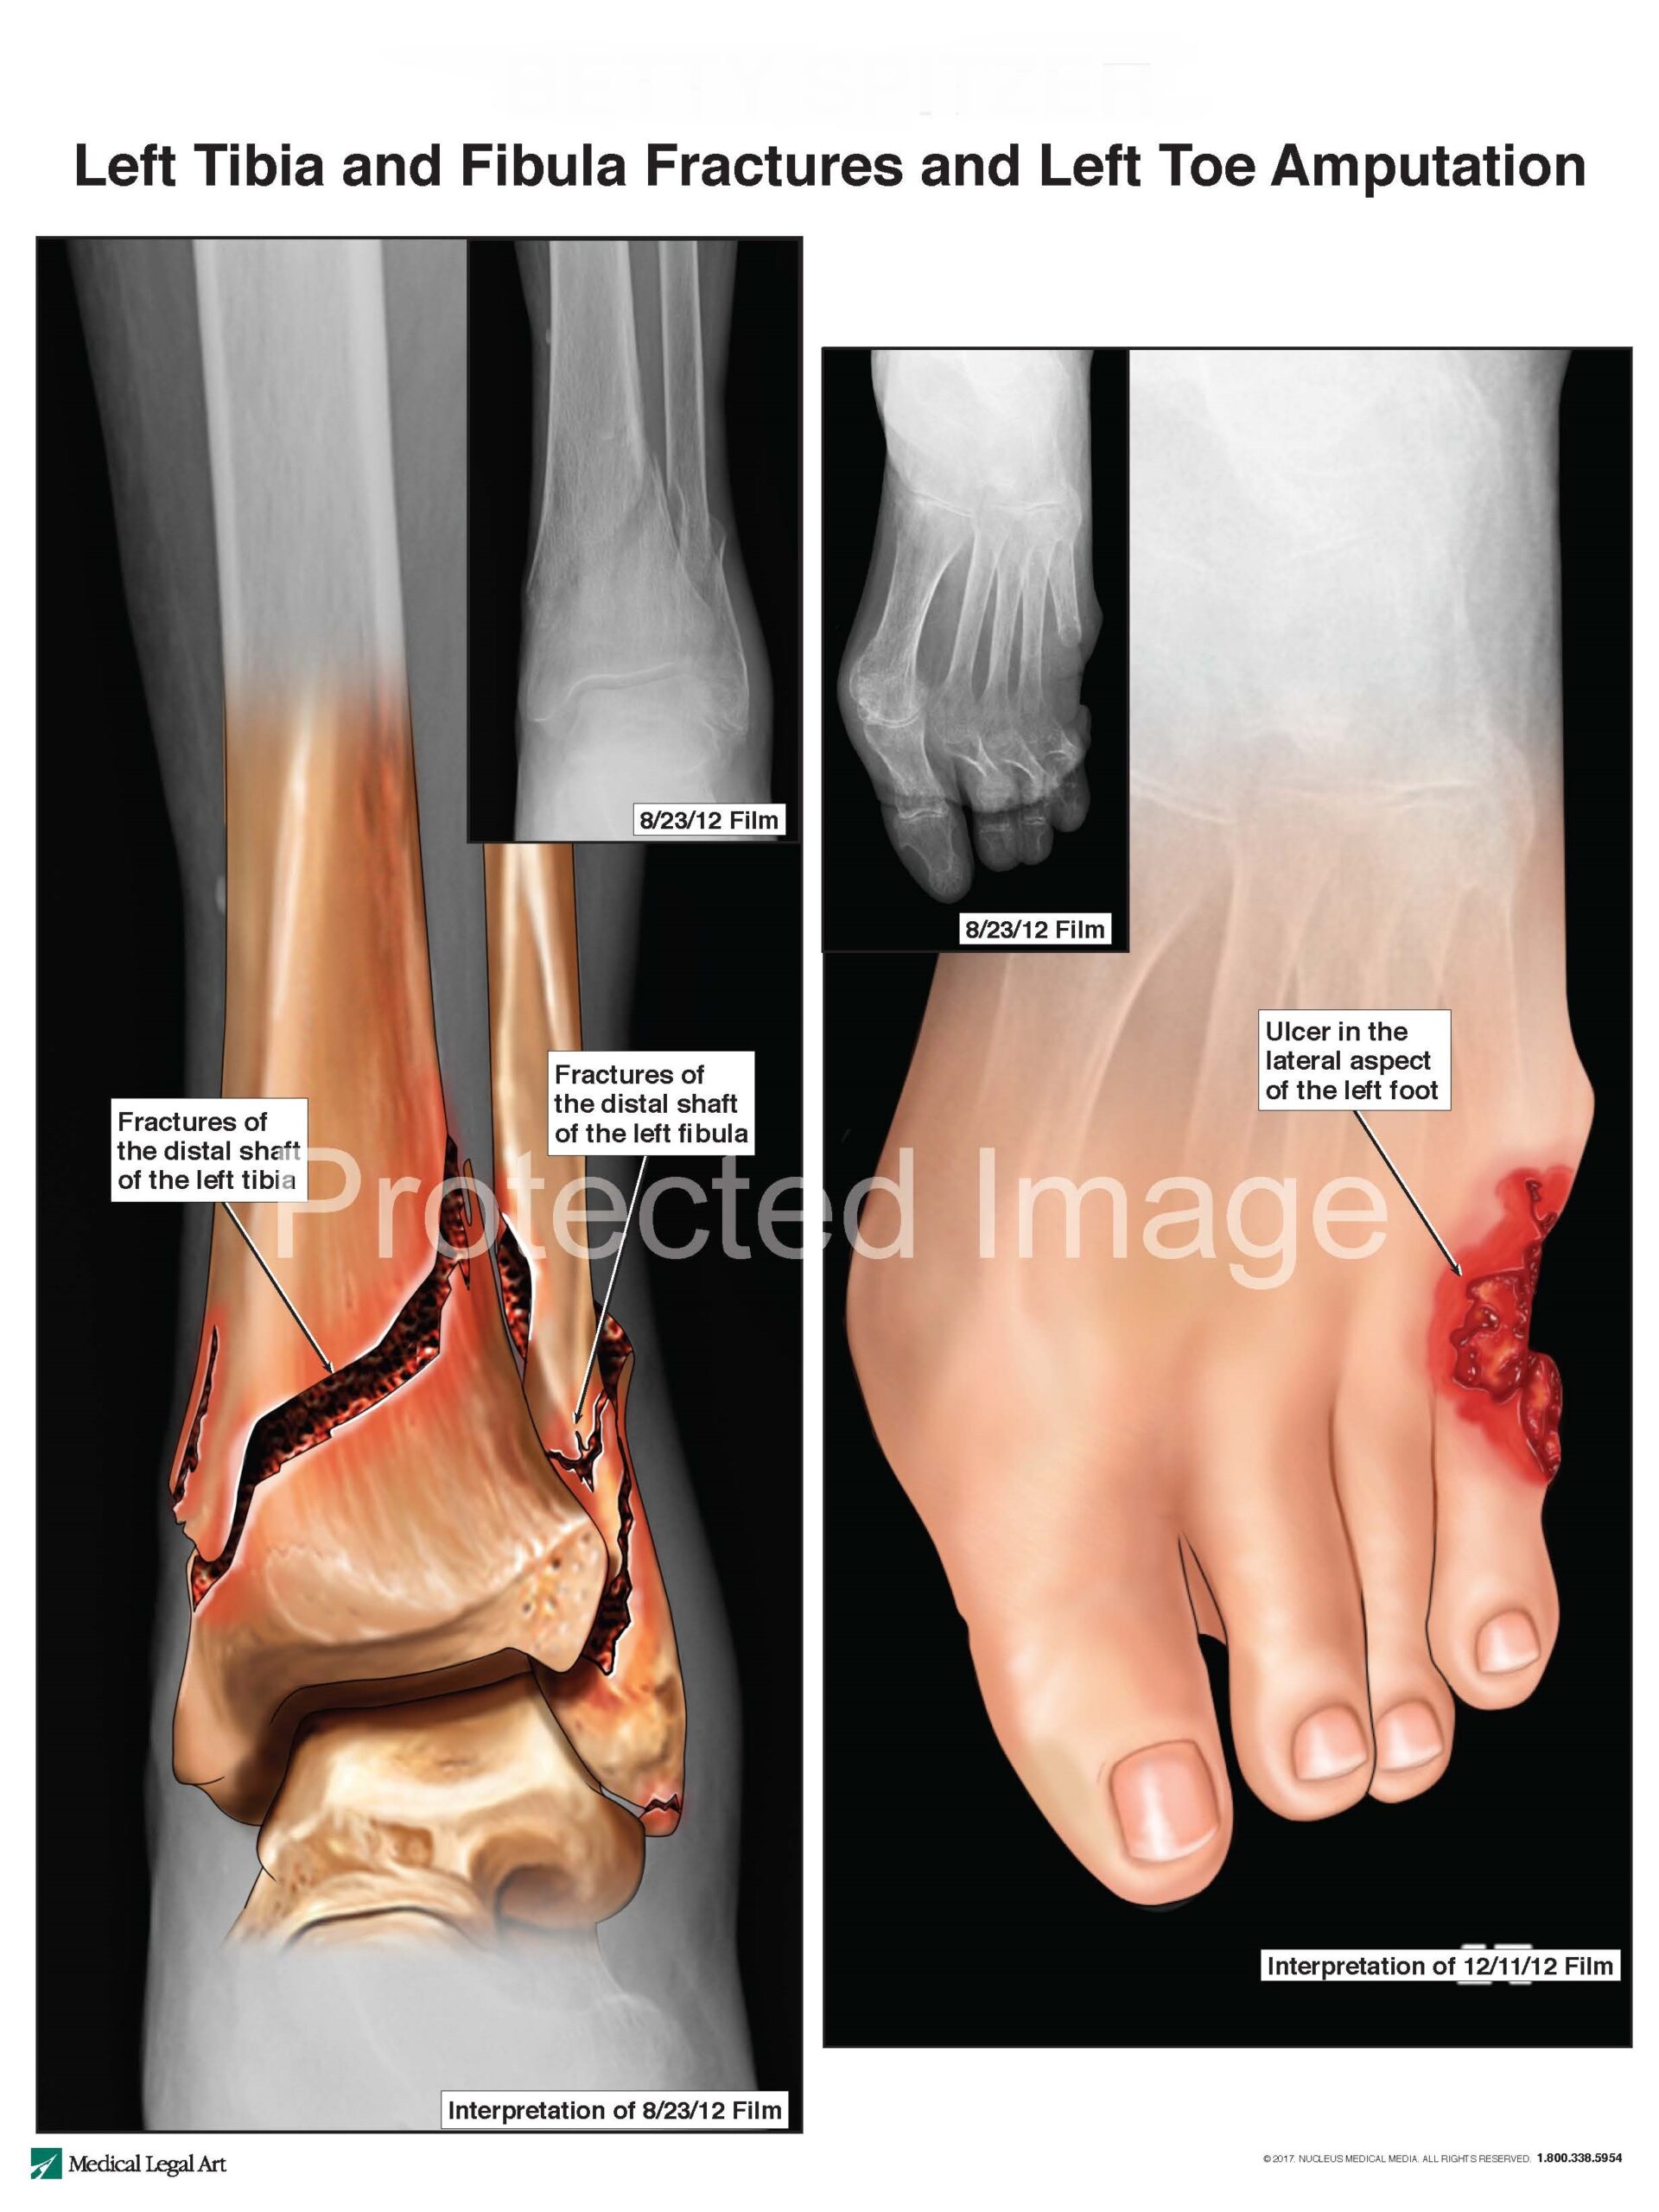

The patient was transported to the hospital, where she was diagnosed with severe fractures of her left tibia and fibula. The patient’s left leg was placed in a leg cast and she was returned to the assisted living facility for post-fracture care.

On September 24, 2012, the patient’s cast was removed and her left leg was placed in a soft brace. When the patient’s treating health care providers removed her cast, they noted pressure ulcers caused by the cast.

The patient also was to have received daily dressing changes and wound care, but the assisted living facility failed to provide that care as the patient’s pressure ulcer care needs required. For example, the patient’s family observed that her wound dressing had, on at least one occasion, not been changed for 23 straight days, the result of which, as observed by those present, were large black wounds on the patient’s foot. The assisted living facility’s failure to change the patient’s wound dressing for 23 days was confirmed by assisted living staff. By way of further example, the facility failed to change her wound dressing daily as ordered between November 11, 2012 and November 16, 2012.

The patient was later seen by her treating physician, who noted she was “at risk for gangrenous changes” and may require an “above the fracture-site amputation.” The patient’s pressure ulcers indeed resulted in gangrene and made necessary an amputation. Her pressure ulcers were also the source of additional infection and sepsis. The patient died December 27, 2012.